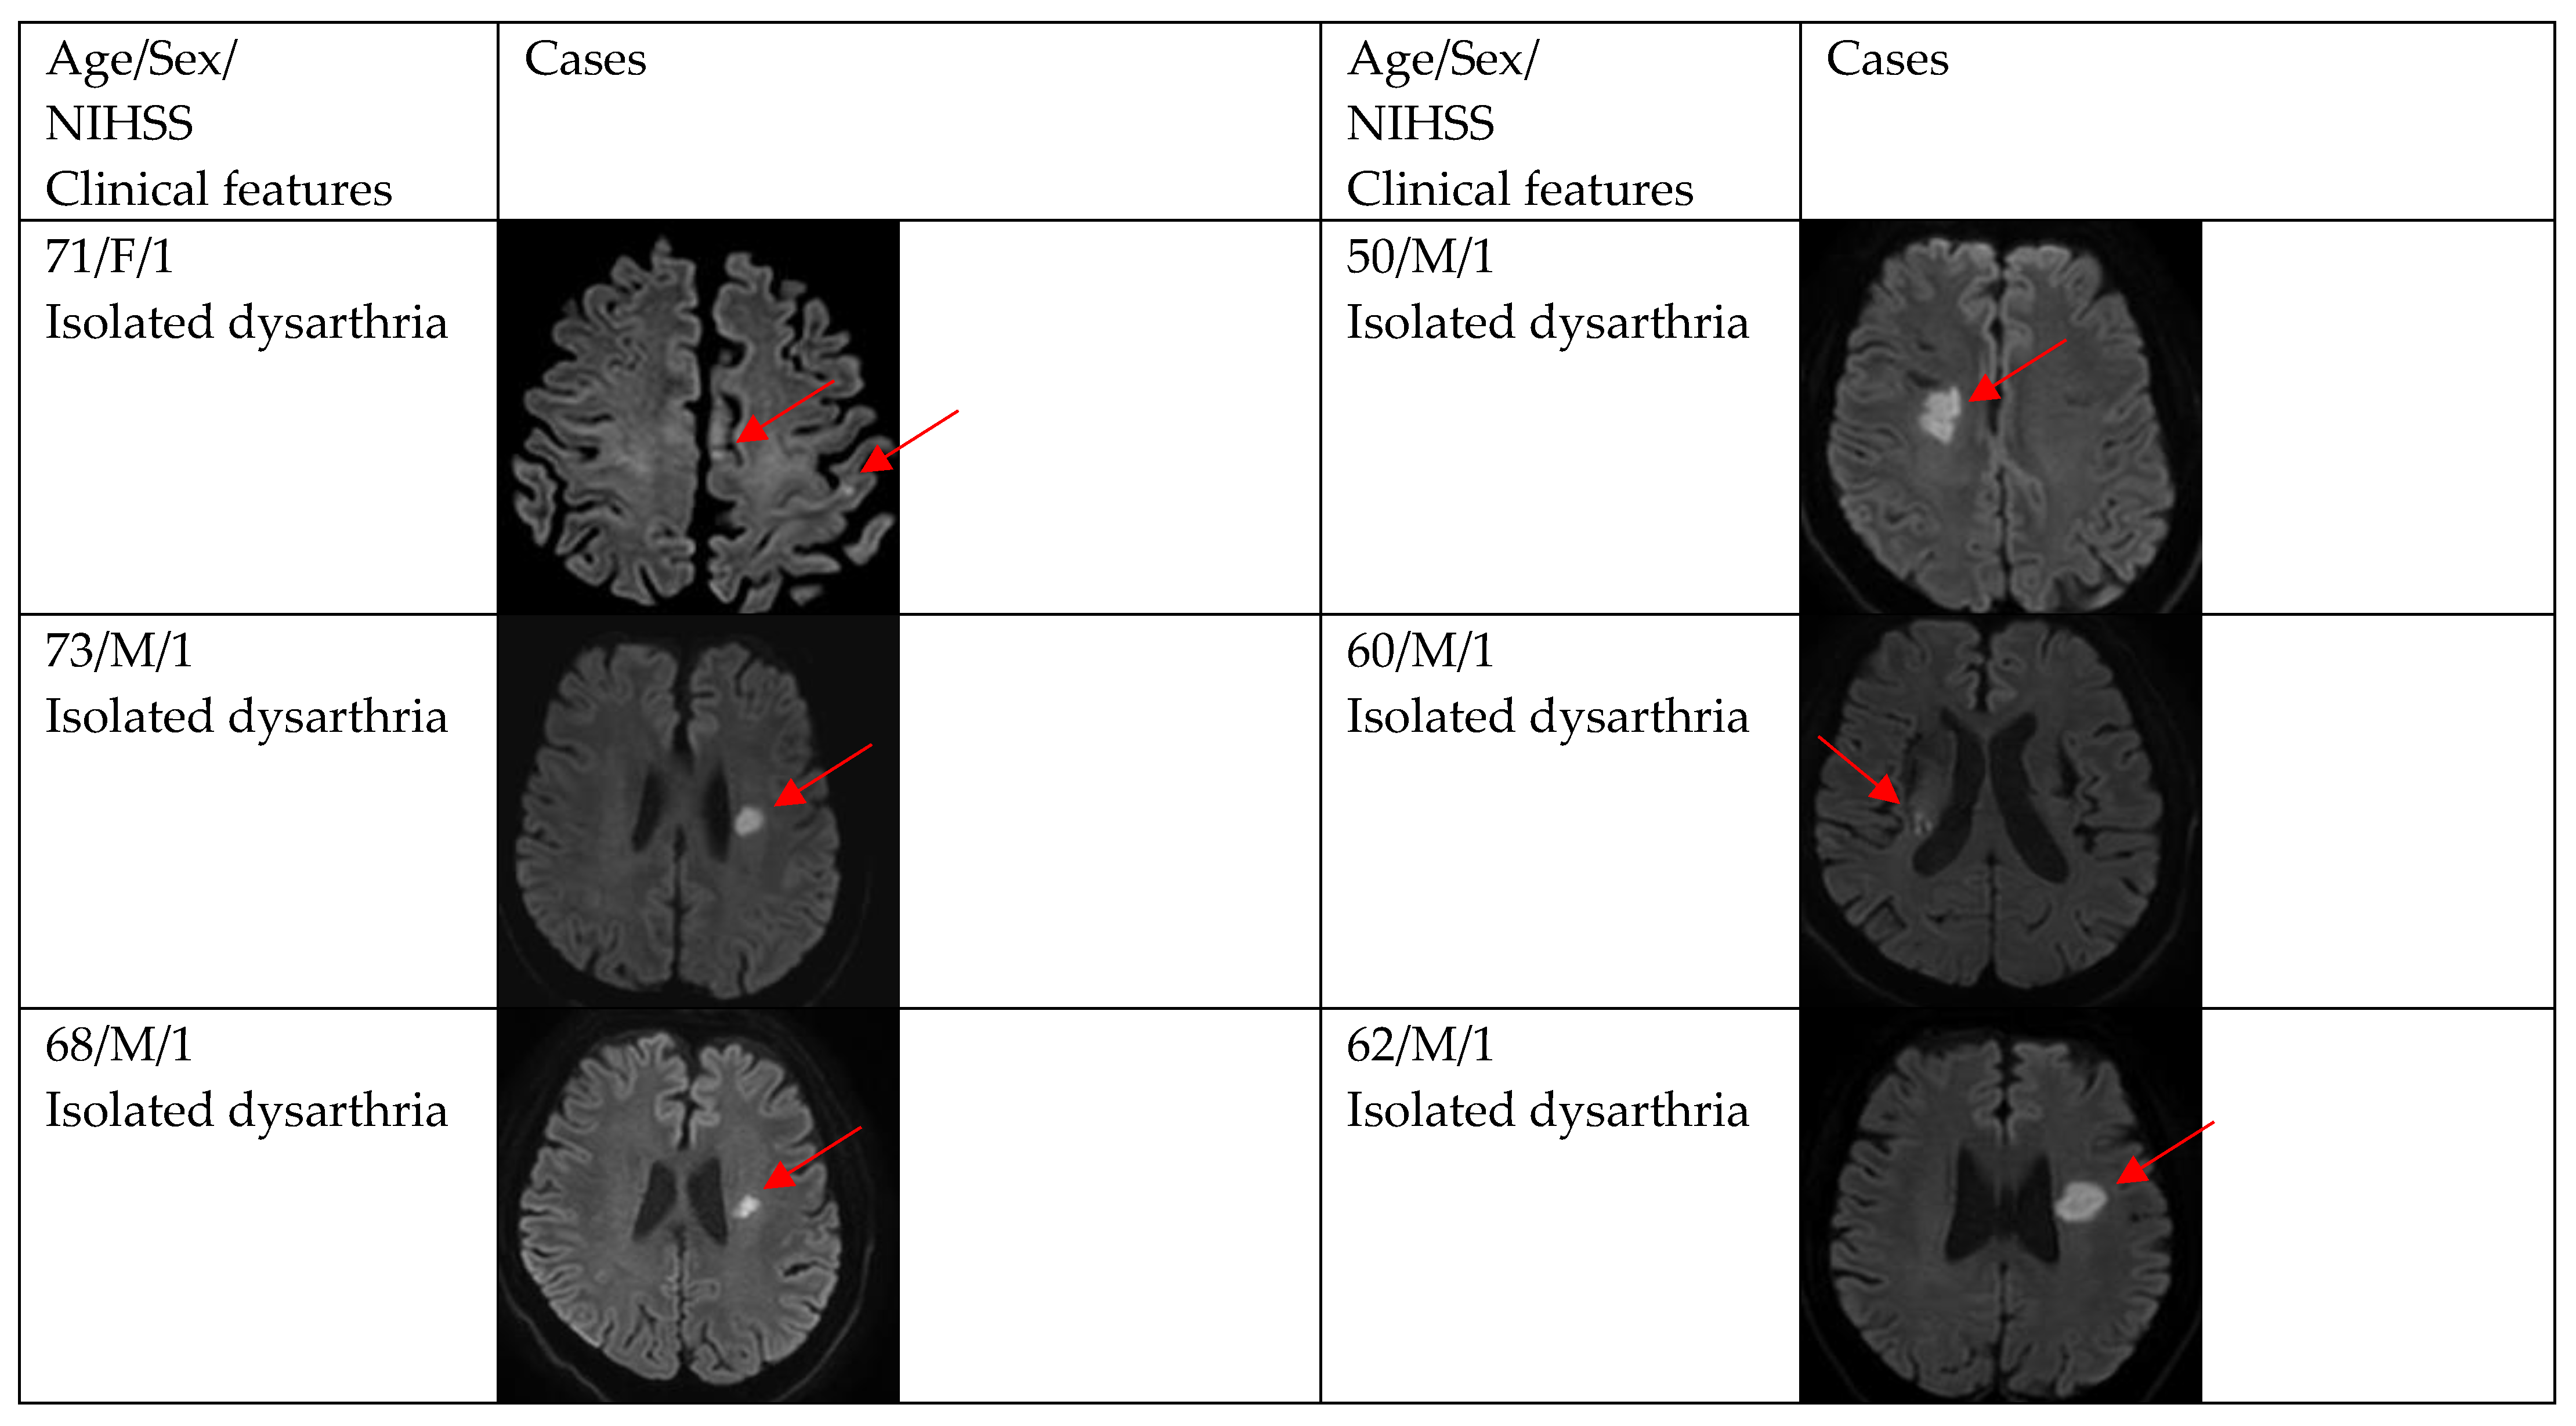

| DWI positivity | 12 (66.7) | 29 (87.9) | 0.154 |

| Single and small lesion | 10 (83.3) | 16 (55.2) | |

| Multiple or territorial lesions | 2 (16.7) | 13 (44.8) | |

| NIHSS at admission to ED in DWI positivity | <0.001 | ||

| 0 | 2 (16.7) | 3 (10.3) | |

| 1 | 11 (83.3) | 4 (13.8) | |

| 2 | 0 (0.0) | 14 (48.3) | |

| 3 | 0 (0.0) | 5 (17.2) | |

| 4 | 0 (0.0) | 3 (10.3) | |